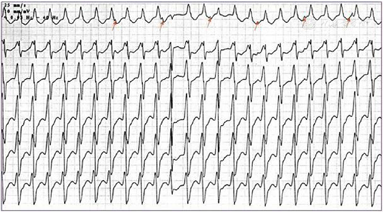

(1)外院心电图示:室性心动过速、ST-T改变(图1)。(2)外院动态心电图之一(1996年6月4日):平均心率77次/min,最快129次/min,最慢56次/min;见个别室早<64次;"RonT"、"插入性室早"、"室早成对"、"室性心动过速"等均系伪差干扰电脑误判,无ST-T改变(监护23 h)。(3)外院动态心电图之二(2019年8月6日):平均心率64次/min,最快94次/min,最慢52次/min;室性早搏936次,有1次成对室早,49阵室性二联律,无室性心动过速;房性早搏9个(4)上海交通大学医学院附属瑞金医院心电图(图2):QRS时限短,T波低平,I、avL肢导低电压。(5)胸X线:两肺纹理略多,未见确切活动性病变。(6)超声心动图(图3):心腔大小及厚度:左房内径33 mm,左室舒张末期内径52 mm,左室收缩末期内径41 mm,室间隔厚度6.5 mm,左室后壁厚度7.5 mm。二维:左室偏大,左室壁不增厚且心肌厚度不均匀,心尖处最薄,部分区域心肌组织较疏松。静息状态下左室壁各节段收缩活动减低,尤以心尖部最明显。各心瓣膜未见明显增厚,开放不受限。右室壁未见明显变薄。左心功能测定:左室舒张末期容量118 ml,左室收缩末期容量63 ml,左室射血分数46%,左室短轴缩短率23%,每搏输出量55 ml。结论:左室壁心肌厚度不均匀,心尖处较薄,部分区域心肌组织较疏松,综合考虑心肌病可能较大。(7)为进一步明确病因,完善冠状动脉造影,结果提示大致正常(图4)。(8)CMR:左室壁心肌厚度不均,左室前壁及心尖处较薄,增强后左室前壁心内膜下可见片状强化,未见反常运动和矛盾运动,左室射血分数41%。结论:左室壁心肌厚度不均匀,左室功能不全,提示非缺血性心肌病变(心肌致密化不全可能,图5)。

本例患者病程中以宽QRS心动过速为主要表现,是指QRS波宽度>120 ms的心动过速,可见于心房颤动伴预激、室上性心动过速伴差传、室性心动过速、起搏心律。其中,室性心动过速心电图的鉴别要点主要包括以下几点:(1)房室分离(图6);(2)室性融合波;(3)窦性夺获(图7);(4)无人区电轴(图8);(5)QRS波同向性(图9);(6)QRS波时限(>150 ms)。室性心动过速除见于缺血性心肌病外,还多见于扩张性心肌病早期、心肌致密化不全、致心律失常性右室心肌病、心肌炎后遗症等。一般情况下,需要植入ICD预防心脏猝死。